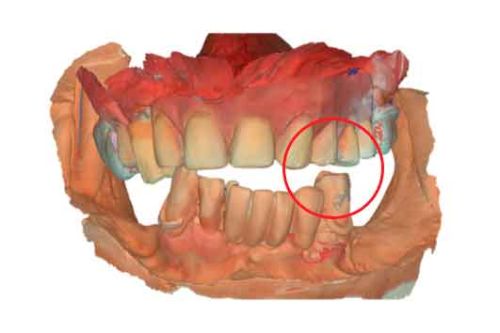

Modèles 3D - Occlusion obtenue par la caméra intra-orale

étape 2 – Acquisition du CBCT

Lorsque les scans IOS traditionnels manquent de références nécessaires, les données du CBCT peuvent servir d'alternative viable. En utilisant les fichiers du CBCT, le clinicien peut établir des références anatomiques précises pour la planification du traitement.

Pour pouvoir utiliser les données CBCT comme modèles initiaux, nous devons transformer le fichier DICOM en un fichier STL. Découvrez-en plus sur la segmentation CBCT et son utilisation dans TWIM ci-dessous.

Avant d'acquérir le CBCT, j'ai ajouté 2 morceaux de composite à la mandibule pour pouvoir effectuer le processus de picking pendant le protocole MODJAW. Il s'agit d'une astuce utile à retenir en cas d'absence de dents.